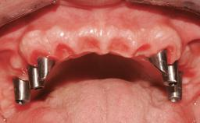

Fixed and removable prosthodontic implant therapy for restoration of the edentulous maxilla is both complex and challenging. Careful assessment and planning is needed in each individual case to explore whether a fixed or a removable solution will be the more suitable to satisfy the patient’s preference for optimal esthetics, phonetics, comfort and function. This Learning Pathway explores the prosthodontically driven treatment planning based on structured assessment, considered diagnosis and practical application in clinical case examples.

Edentulous Maxilla Fixed vs. Removable Prosthodontics Planning Principles Prosthodontic Planning & Procedures Prosthodontic Planning & Procedures